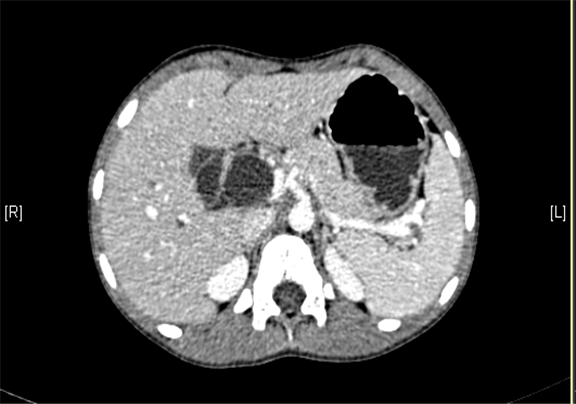

上腹部增强CT:肝内外胆管扩张,考虑胆管囊肿(以左右肝管、肝总管及胆总管扩张明显)可能性大。

术前CT检查:

静脉期